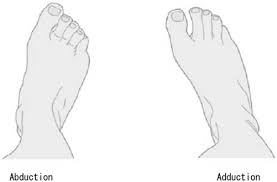

in what plane does abduction and adduction of the foot occur?

transverse plane

what are the motions of pronation of the foot?

everesion

abduction

what are the motions of supination of the foot?

inversion

adduction